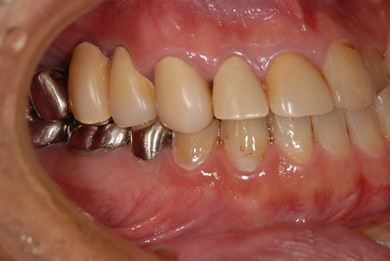

| 性別/年齢 | 男性 / 53歳 | ||||||||||||||||||||||||||||||||

| 主訴 | 左下奥歯2本のインプラント治療を希望。 | ||||||||||||||||||||||||||||||||

| 治療方針 | 左下欠損部分をインプラント治療にて機能的・審美的回復を行う。 | ||||||||||||||||||||||||||||||||

| 治療内容 | インプラント2本、ハイブリッドセラミッククラウン2本 | ||||||||||||||||||||||||||||||||

| 総治療費 | 399,000円 | ||||||||||||||||||||||||||||||||

| 治療期間 | 9ヶ月 |